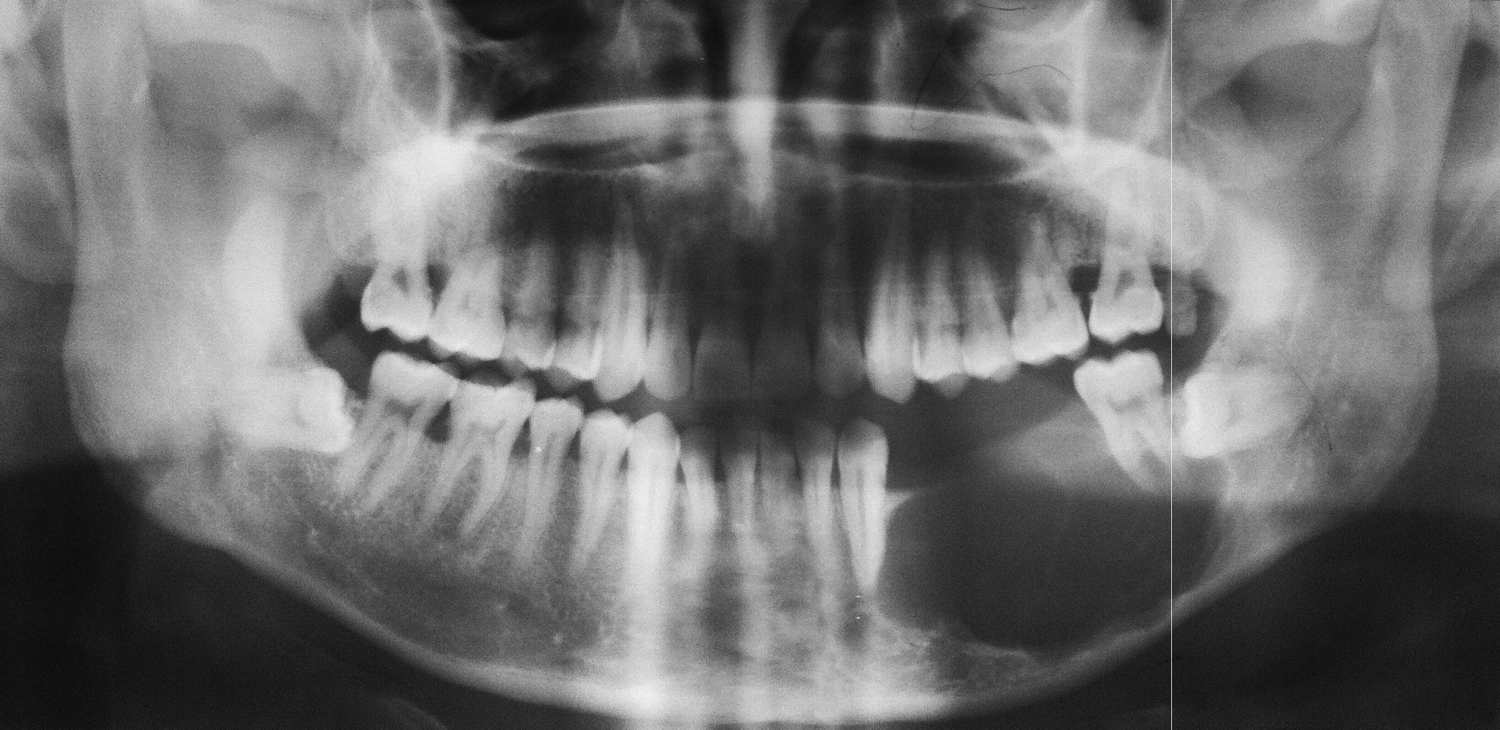

Oral Diagnoz ve...

Oral diagnoz, diş hekimliğinde ağız içerisindeki hastalıkları ve belirtiler veren sistemik rahatsızlıkların ortaya çıkması için...

Devamını Oku